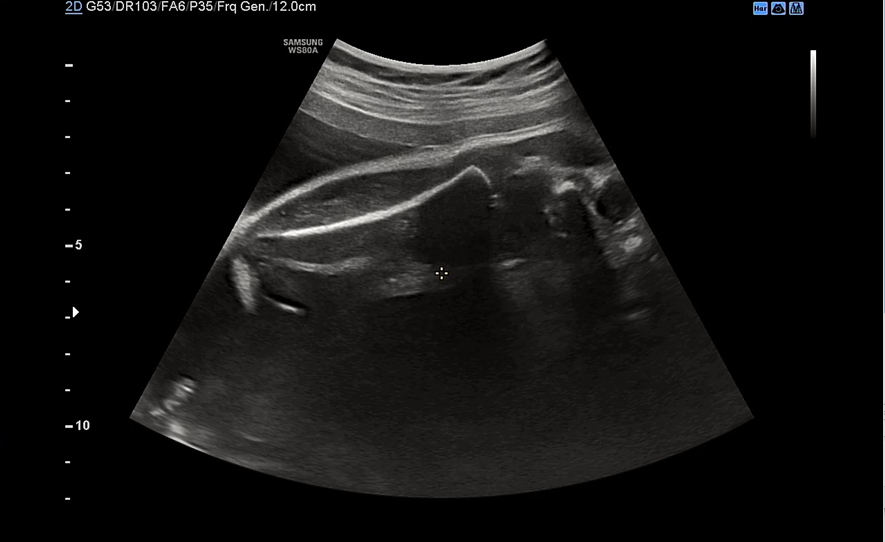

심장도 여전히 잘 뛰고 있고 bpd 7.67cm, ac 26.65cm 정도 나왔다. 원래 주수에 비해 머리가 작은 편이고 배는 딱 적당한 편이었는데 이번주에는 복부가 빵빵해졌다.

다리는 5.96cm 정도로 평균보다 긴 편이라고 하셨다.

이 날 우리 아기는 배에 얼굴을 파묻고선 얼굴을 보여주지 않았다. 아니 지난주에는 그렇게 잘 보여주더니 이번엔 얼굴을 돌릴 기미가 1도 안보였다. 요건 얼굴을 돌린 상태에서 귀만 살짝 보여준 모습.